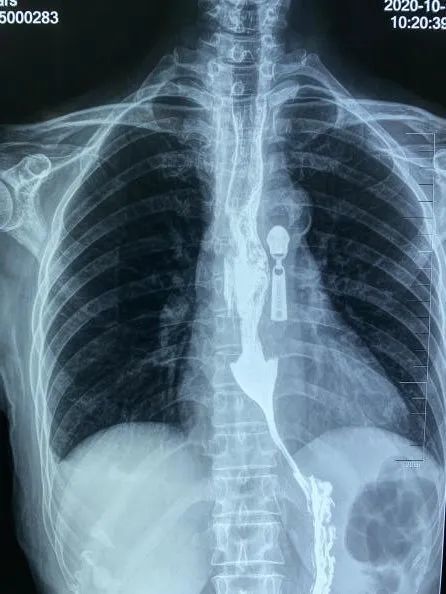

唐兴耐心地为她做检查,经上消化道钡餐(钡餐检查是检查消化道的一种常用方法)发现其食管下端呈“鸟嘴样”改变,同时结合食管测压报告和患者病史,诊断钟阿姨患有贲门失弛缓症。

贲门为食道和胃的接口部分,是胃上端的入口。该病是由于贲门部肌肉功能障碍,持续收缩痉挛的贲门部肌肉如同“紧箍咒”一般束缚着患者的食管,从而引发不适症状。

“食管下端贲门肌肉增厚、痉挛,人吃下去的食物堆在食管里头,不容易进入胃里面。患者表现为有饥饿感、有食欲,老想吃,但吃几口就要吐。”唐兴解释说,患贲门失弛缓症的病人很痛苦,它的发病率是十万分之一左右。